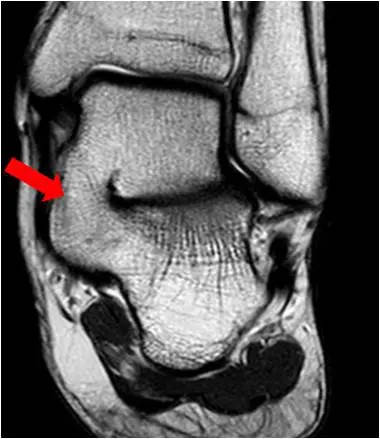

Bildgebende Diagnostik

Eine Röntgendiagnostik gibt dann häufig bereits erste Hinweise auf das Vorliegen einer Koalitio, die durch ein entsprechendes schnittbildgebendes Verfahren (MRT und-oder CT) gesichert werden. Kalkaneo-navikulare Koalitiones lassen sich im schrägen Röntgenbild gut darstellen. Talo-kalkaneare Koalitiones sind im konventionellen Röntgenbild nur durch indirekte Röntgenzeichen (Talar beak, C-Sign) erkennbar. Im CT und MRT ist dann die Diagnose zu bestätigen.